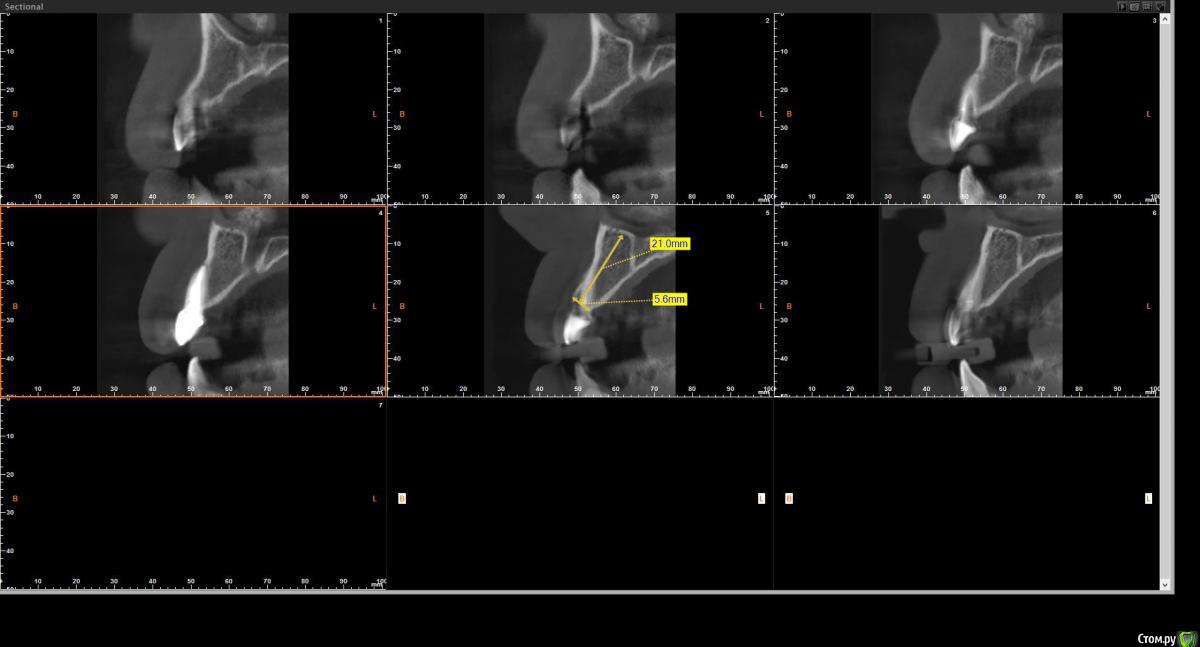

Tari Опубликовано 15 июня, 2016 Поделиться Опубликовано 15 июня, 2016 Зуб 2.2 произошла фрактура корня, по вестибулярной поверхности свищевой ход. Понятно, что зуб под удаление. Не могу определиться с хирургией по КТ (одномометная имплантация, сохранена ли вестибулярная кость, нужна ли будет нкр) и какую временную ортопедическую реабилитацию предложить(временная коронка,косметическая пластинка).Если срезы не понятны-выложу другие. Ссылка на комментарий

Tari Опубликовано 15 июня, 2016 Автор Поделиться Опубликовано 15 июня, 2016 Я не пойму по кт и т.к есть свищ, там сохранена кортикалка или нет. Похоже, что нет.Или я не так смотрю? Ссылка на комментарий

kamranchick Опубликовано 15 июня, 2016 Поделиться Опубликовано 15 июня, 2016 По кт крайне редко кортикалку можно увидеть во фронте, есть свищ и бог с ним)) откюретажите, а закрутится есть место у вас вагон. Ссылка на комментарий